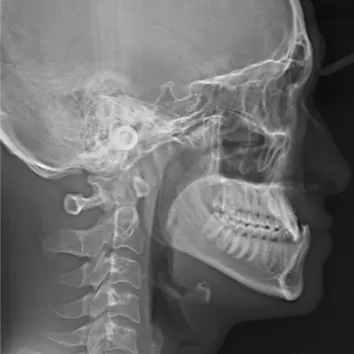

Rayons X avant le traitement

[Radiographie panoramique/Céphalogramme latéral]